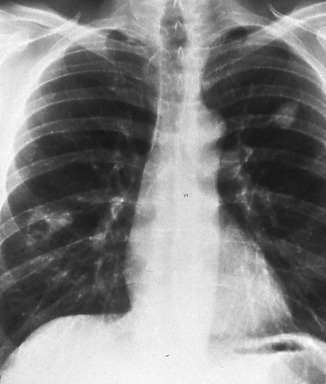

LUNG

CANCER

A Handbook for Staging, Imaging, and Lymph Node Classification

by Clifton F. Mountain, MD; Herman I.

Libshitz, MD; and Kay E. Hermes |